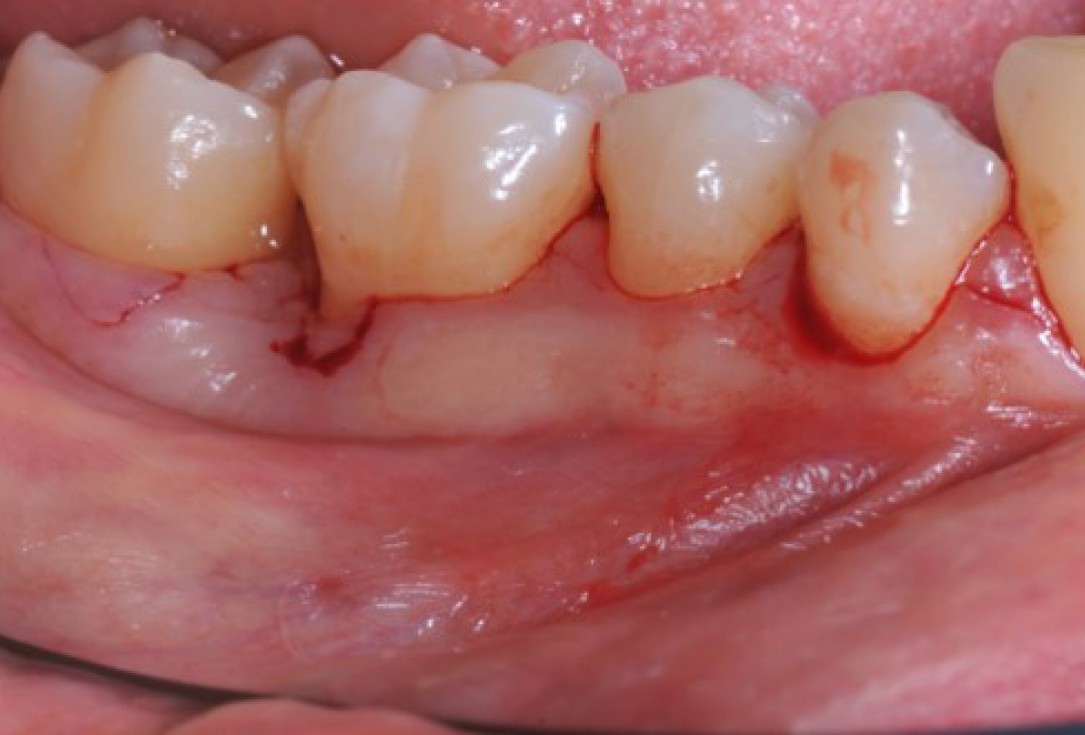

05/22 - Access flap (simplified papilla preservation technique between #44 and #45 and amplified papilla preservation technique between #47 and# 46). Buccal view.

Deep intrabony defects treated using Straumann® Emdogain® - Dr. M. Stefanini